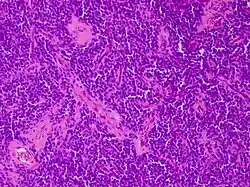

Los tumores vaginales son neoplasias que se encuentran en la vagina. Pueden ser benignos o malignos.[1] Una neoplasia es un crecimiento anormal de tejido que generalmente forma una masa de tejido.[2][3][4] Las neoplasias vaginales pueden ser sólidas, quísticas o de tipo mixto.[5]

Los cánceres vaginales surgen del tejido vaginal, y los sarcomas vaginales se desarrollan a partir de hueso, cartílago, grasa, músculo, vasos sanguíneos u otro tejido conjuntivo o de soporte.[6][7] Los tumores en la vagina también pueden ser metástasis (tejido maligno que se ha diseminado a la vagina desde otras partes del cuerpo).[8][7] El cáncer que se diseminó desde el colon, vejiga y estómago es mucho más común que el cáncer que se origina en la vagina.[9] Algunos tumores benignos pueden progresar hasta convertirse en tumores malignos, como los cánceres vaginales.[10][11] Algunos tumores neoplásicos de la vagina son lo suficientemente raros como para describirse solo en estudios de casos.[3]